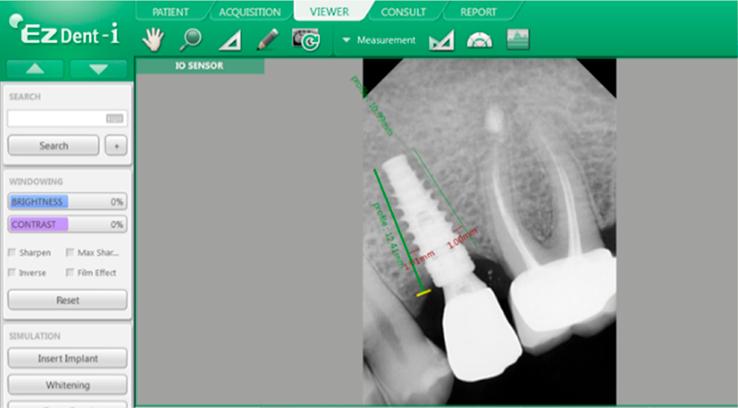

Digital radiographs of 28 implants were taken and evaluated at four intervals: preoperatively, 1 and 3 months postoperatively, and 2 months following placement of the permanent prosthesis. Gray values were measured in different areas around the implants through analyzing X-ray images and measuring bone density around the implants using EzDent - 2D software. The aim of this study was to investigate changes in bone density around implants in three regions: apex, neck, and body, as well as to record average density values during the observation period by measuring digital image gray levels (the gray values of the digital radiographs). This was conducted to determine local bone densities in dental implant recipient sites and to study changes in local bone densities at different intervals, preoperatively and postoperatively and after placement of the prosthesis.

A decrease was observed in gray values proportional to reference values 1-month after implant insertion, but these increased at 3 months after insertion and continued to rise 2 months after placement of the prosthesis in the apical, body, and neck regions of the implant.